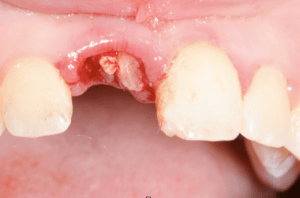

Fractured Tooth and Dental Implant Replacement in an Hour

This case highlights a 17-year old female that suffered damage from a car accident to her front tooth.

Fractured Tooth